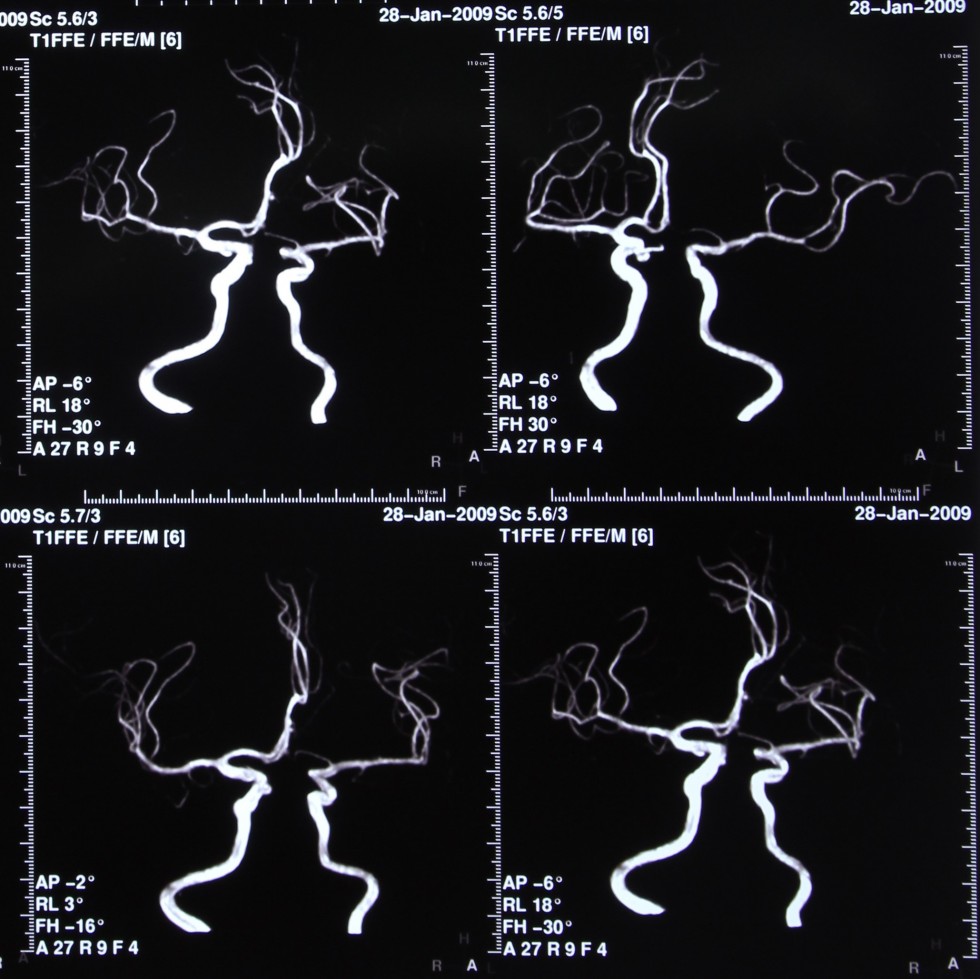

Intracranial MRA

MRA stands for magnetic resonance angiography. It is an MRI study of the blood vessels. MRAs are used to assess abnormalities in the blood vessels of patients with a history of stroke, aneurysm, heart disease, and atherosclerotic vascular disease.